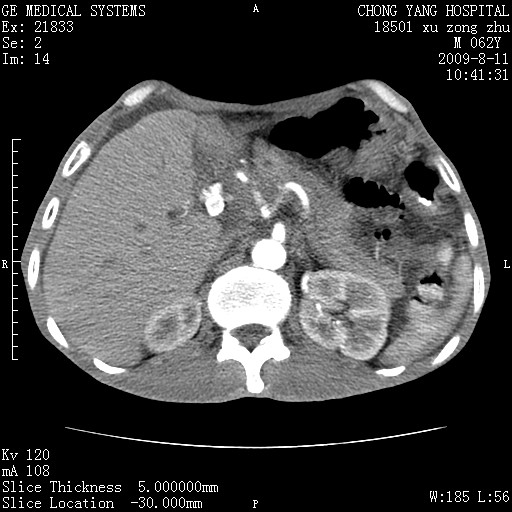

以下是引用杀毒软件在2009-8-11 16:35:00的发言:[br]肝内胆管扩张局限于左叶,胆管内有结石伴肝外胆管结石,胆管壁增厚呈弥漫性并发腹腔积液,胰腺边界模糊。[br][br]考虑---胆总管及肝内胆管结石继发胆管炎及胰腺炎,左肾下极囊肿,腹水。

以下是引用zjzjr在2009-8-11 17:35:00的发言:[br]肝内胆管扩张局限于左叶,胆管内有结石伴肝外胆管结石,胆管壁增厚呈弥漫性并发腹腔积液。[br][br]考虑---胆总管及肝内胆管结石继发胆管炎,左肾下极囊肿,腹水。